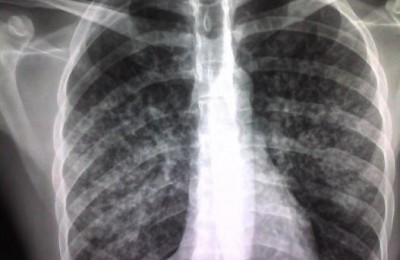

Detectan dos casos de tuberculosis en un albergue municipal de Madrid

El Ayuntamiento de Madrid ha detectado en los últimos días dos casos de tuberculosis en el centro de acogida municipal para personas sin hogar San Isidro, en el...